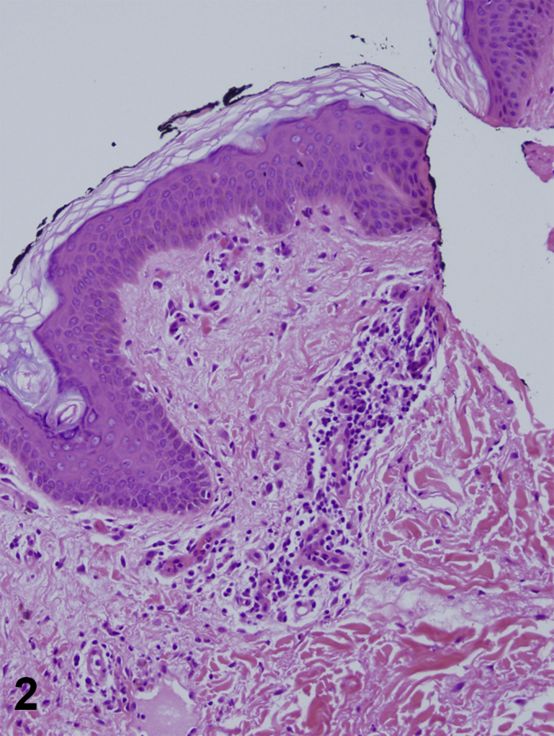

一名39岁妇女,有2周新发双侧腿部疼痛、关节痛和卧床史。此外,患者诉有2天的右膝、右侧腿部、后颈和头皮瘙痒皮疹病史,以及3天的咽喉疼痛和发烧史(每日最高温度39.4°C)。实验室值包括白细胞计数11.1,中性粒细胞90%;血小板469;铁蛋白3662 ;血沉115 ;c反应蛋白225;天冬氨酸氨基转移酶91;丙氨酸氨基转移酶67;抗核抗体(ANA)和类风湿因子阴性。体魄检查发现有剥落、线状、界限不清的紫色丘疹和斑块(图1)。侧翼活检显示交界性皮炎(图2和图3)。

图2